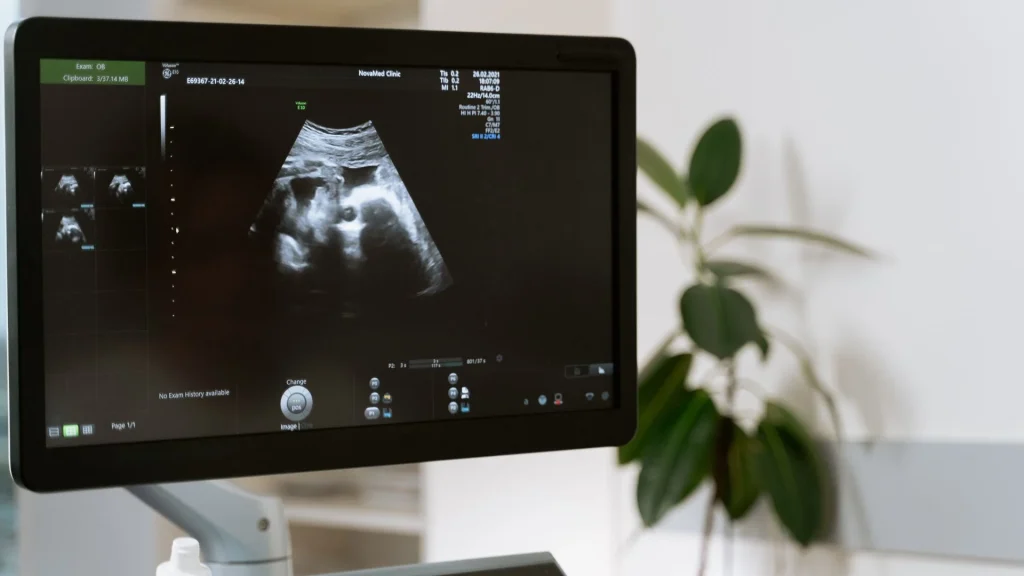

Integrasi AI pada USG membawa perubahan besar dalam pemeriksaan point-of-care karena memungkinkan akurasi tinggi tanpa memerlukan operator sangat berpengalaman. Teknologi ini membantu dokter di ruang IGD, ICU, atau klinik kecil untuk mendapatkan gambaran diagnostik cepat dan tepat. Dengan dukungan AI, USG menjadi alat yang semakin andal untuk penilaian awal pasien.

Sistem AI mampu mengenali organ dan struktur penting secara otomatis sehingga membantu operator mengurangi kesalahan pencitraan. Identifikasi yang presisi mempercepat proses diagnosis terutama pada kondisi darurat. Kemampuan ini meningkatkan efisiensi dan mengurangi variabilitas antaroperator.

AI memberikan arahan langsung mengenai posisi, sudut, dan tekanan probe yang ideal selama pemeriksaan. Panduan visual ini sangat membantu dokter pemula dalam menghasilkan citra yang berkualitas tinggi. Dengan demikian, pemeriksaan menjadi lebih konsisten meskipun dilakukan di lingkungan point-of-care.

Auto measurement yang didukung AI mempercepat proses analisis seperti mengukur diameter pembuluh darah, ketebalan dinding organ, atau volume cairan. Proses otomatis ini mengurangi waktu evaluasi dan meningkatkan keandalan data. Diagnosis dapat ditetapkan lebih cepat, terutama di situasi kritis.